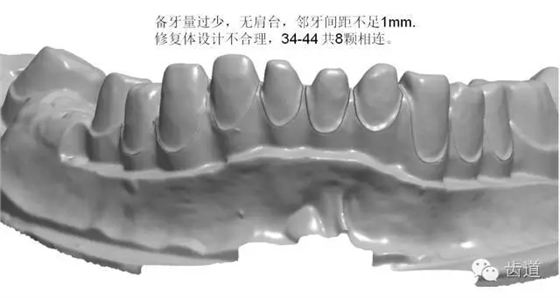

如:無肩臺、凹面肩臺、邊緣線不清晰、雙重邊緣線、備牙空間不足、基牙有倒凹或牙橋沒有共同就位道、基牙切端或頜緣過于尖銳等等。

解決方案:按要求制備基牙 1.將基牙預備成圓緩的斜面肩或軸-頸線角圓鈍的水平直角肩臺,建議制備肩臺寬度為0.5~1.0mm。 2.咬頜面和切端需磨除0.8~1.5mm,軸面聚合角度為3°~6°,軸壁與咬頜面的連接處應圓鈍,轉角半徑大于0.5mm. 3.頜面120°~140°的開放角度可以保證在切削過程中精確的復制出內冠的表面,進而達到完好的密合。 4.連橋制備時要求基牙間具有共同就位道,避免倒凹。